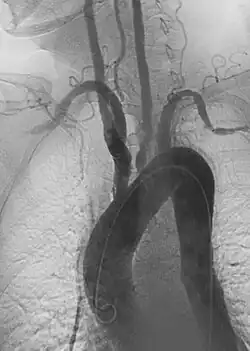

Aortic aneurysms include thoracic, abdominal and thoracoabdominal aneurysms. Treatment strategies are customized depending on the location, size, rate of growth and extent of the aneurysm as well as the medical comorbidities of the patient. For example, an intact, small but slowly growing aneurysm may be safely monitored with serial imaging for months or years before elective repair is considered. Elective endovascular aortic grafting is now routinely attempted when possible. Endovascular aortic repair (EVAR) refers to treatment of an abdominal aortic aneurysm, while thoracic endovascular aortic repair (TEVAR) is performed on the thoracic aorta. A ruptured aneurysm may be taken emergently for open, endovascular or combination repair.

A variety of endovascular grafts are available, and each has advantages and disadvantages depending on the characteristics of the aneurysm and patient.[90]